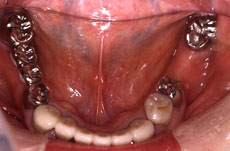

●症例2

術前

術後